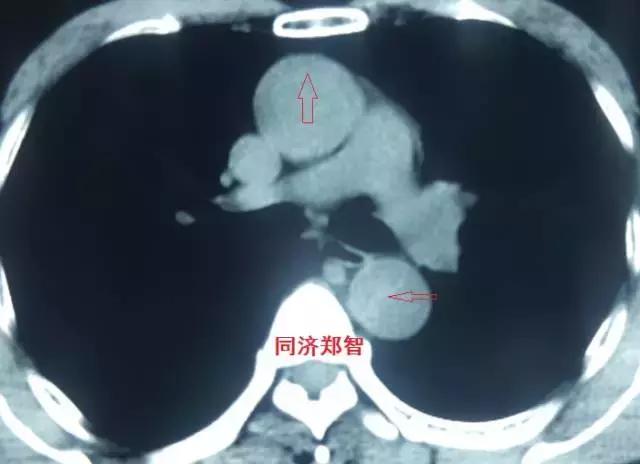

平扫CT提示升主动脉及降主动脉内膜片,CTA证实为A型主动脉壁间血肿。

三

第三招 神奇的钙化点征

正常主动脉的血管可能有钙化,在没有病变的主动脉壁,钙化点一般在主动脉外周一圈,当血管内出现内移的钙化点,则提示内膜片内移,可能是病变的征象。

病例九

平扫CT提示降主动脉内膜片征,同时内膜片中可见一钙化点。CTA证实为B型主动脉夹层。